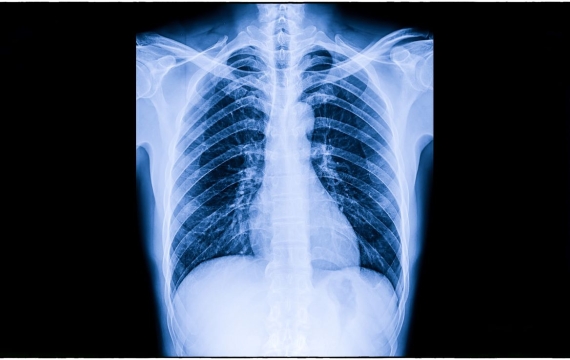

Una radiografía es una prueba radiológica que permite obtener imágenes de los huesos, órganos y tejidos del cuerpo, mediante el uso de rayos X. Las partes más densas aparecen en los resultados en diferentes tonos en una escala de grises.

A diferencia de las radiografías, la ecografía no utiliza radiación. La ecografía también puede mostrar partes del cuerpo en movimiento, por ejemplo, el corazón latiendo y la sangre fluyendo por los vasos sanguíneos.